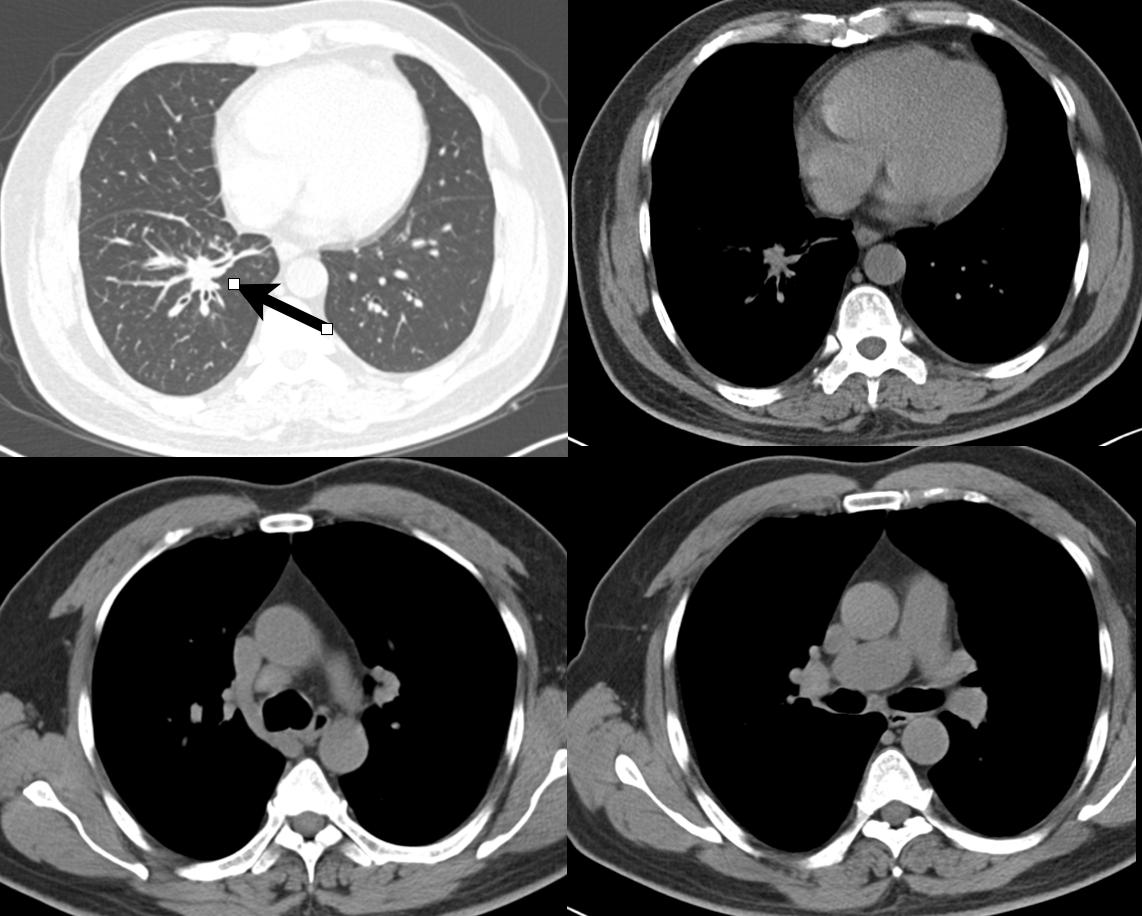

患者行胸部CT后,入院,进一步行支气管镜活检,病理确诊右肺下叶基底段腺癌(cT4N3M1c IVB期) , 纵隔、锁骨下淋巴结转移。

胸部CT提示右肺下叶基底段支气管壁不均匀增厚,局部不规则结节灶,纵隔及右侧肺门淋巴结增大。病理证实腺癌